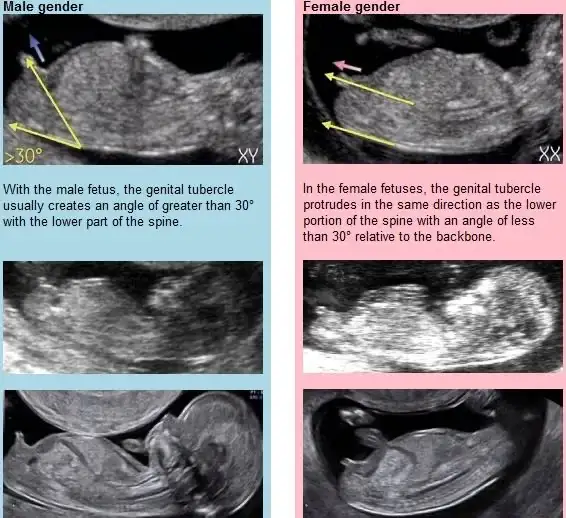

Nub teorisi. Oglum da 9. Haftada oğlan dedim doktor kıza benzetti aradaki kordon olabilir diye 11. Hafta da erkek olduğunu öğrenmiştim

Ben neden anlamıyorum şu nub olayını ya.

Gerçekten merak ediyorum neresine bakıyorsunuz tam olarak?